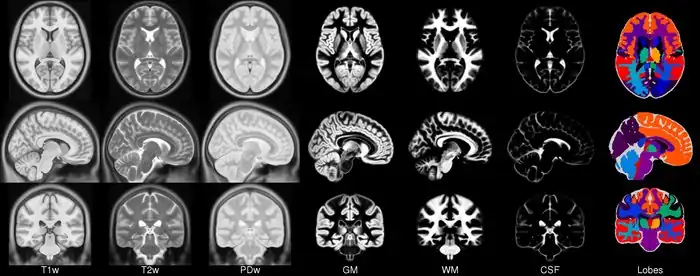

In 2001, within the context of the ICBM project (19) a concerted effort was undertaken by three sites (MNI, UCLA, RIC) to collect a set of full- brain volumetric images from a normative population specifically for the purposes of generating a model. 152 new subjects were scanned using T1, T2 and PD sequences as the MNI’s part of the ICBM project using a specific protocol (27). These images were acquired at a higher resolution than the original average 305 data and exhibit improved contrast due predominately to advances in imaging technology. Each individual was linearly registered to the average 305 and a new model was formed. In total, three models were created at the MNI, the ICBM152_T1, ICBM152_T2 and ICBM152_PD from 152 normal subjects. This resulting model is now known as the ICBM152 (although the model itself has not been published). One advantage of this model is that it exhibits better contrast and better definition of the top of the brain and the bottom of the cerebellum due to the increased coverage during acquisition.

The entirely automatic analysis pipeline of this data also included grey/white matter segmentation via spatial priors (41). The averaged results of these segmentations formed the first MNI parametric maps of grey and white matter. The maps were never made publicly available in isolation but have formed parts of other packages for some time including SPM, FSL AIR and as models of grey matter for EEG source location in VARETTA and BRAINWAVE.

In addition to the standard analysis performed on the ICBM data, 64 of the subjects data were segmented using model based segmentation. 64 of the original 305 were manually outlined and a resulting parametric VOI atlas built.